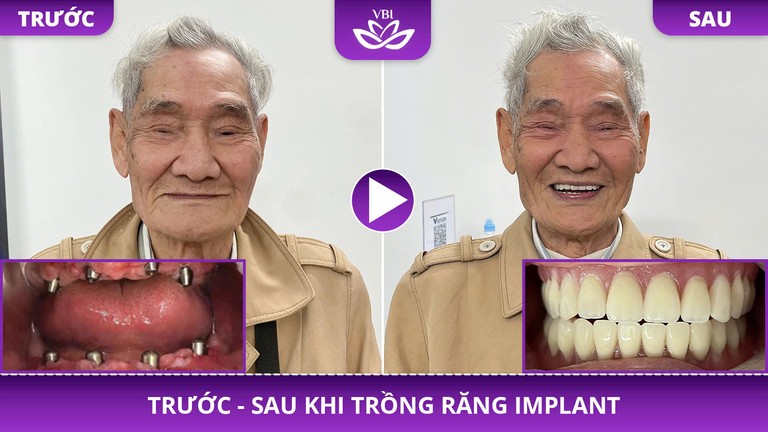

Mất Răng Toàn Hàm

- Ăn nhai khỏe như thật

- Ngăn tiêu xương, giữ nét

- Tự tin cười, giao tiếp

Khách Hàng Nói Gì Sau Khi Trồng Implant?

Hàng nghìn khách hàng đã lấy lại nụ cười tự tin. Đây là câu chuyện thật từ những người đã trải nghiệm dịch vụ tại Nha Khoa Việt Bỉ.

Implant răng hàm dưới

Trụ Hàn Quốc – Phục hình hoàn tất

Implant răng cửa

Trụ Thụy Sĩ – Thẩm mỹ tự nhiên

Implant răng hàm trên

Trụ Mỹ – Ăn nhai vững chắc